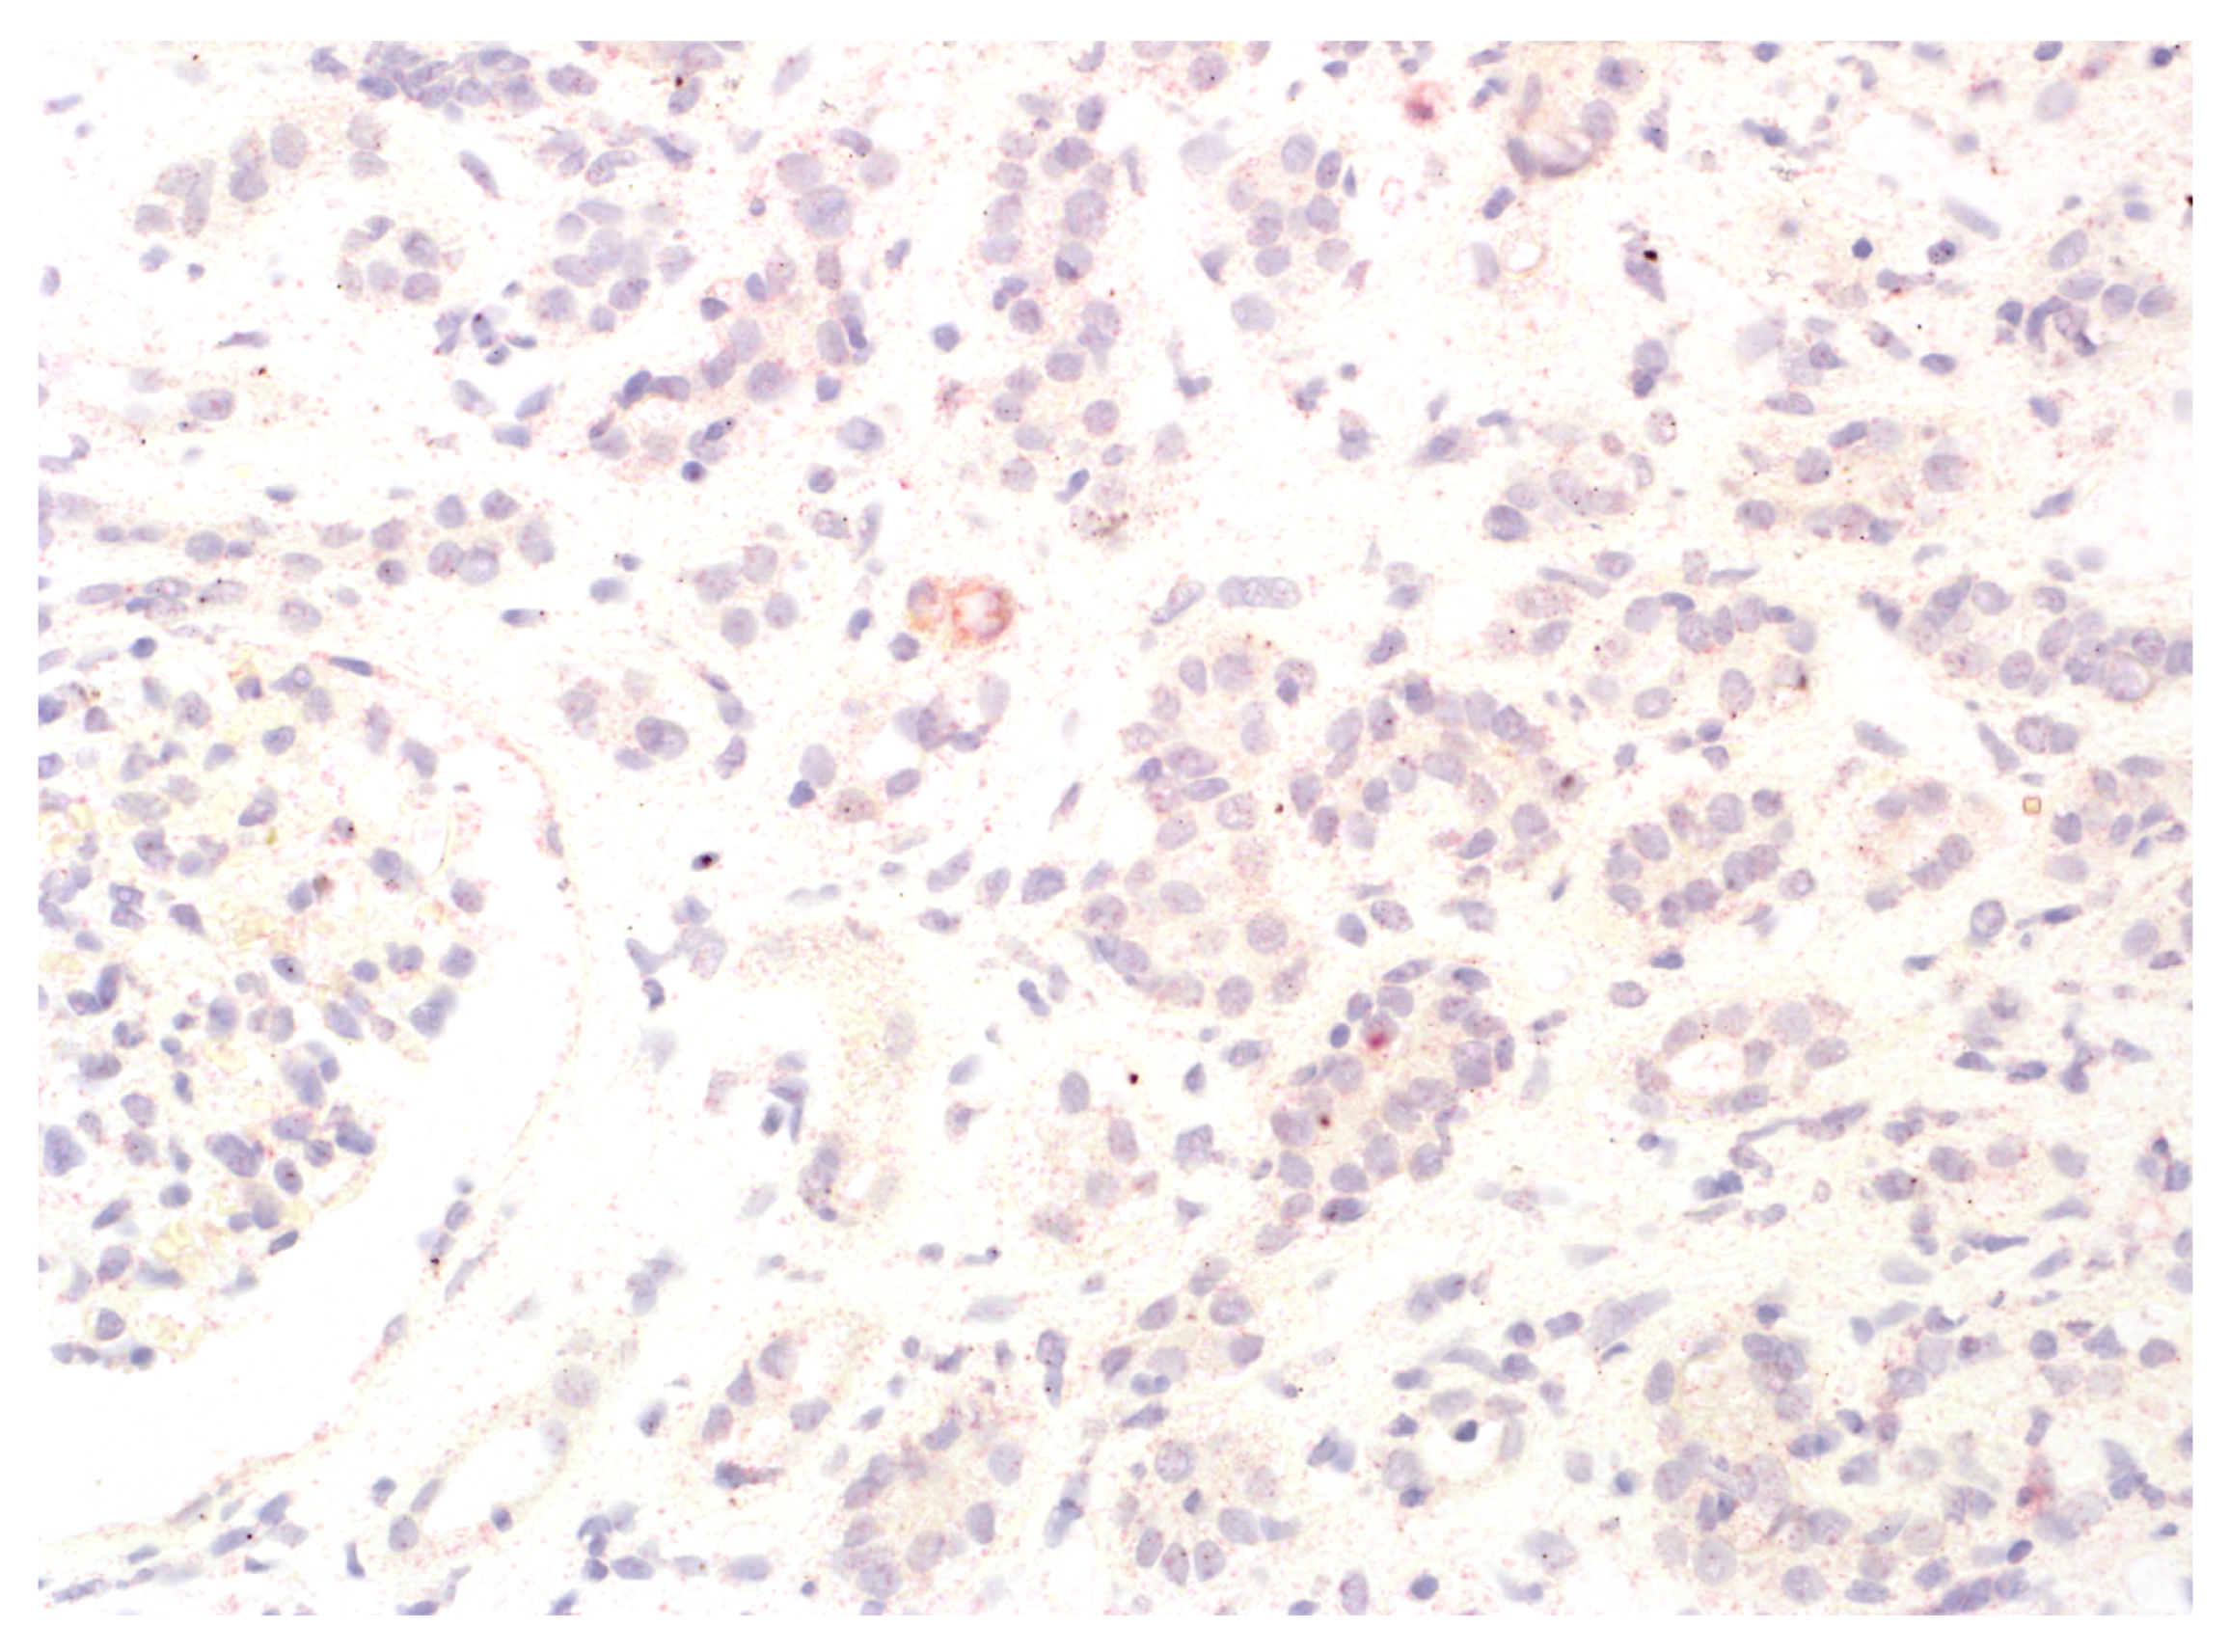

Figure 1.

Lack of IDO1 reactivity in the interstitium.

Figure 2.

No IDO1 expression in the interstitial immune cells. Focal IDO1 immunoreactivity in tubular epithelium with moderate to severe atrophy.

We analysed the expression of IDO1 in interstitial foci. The scoring system for IDO1 expression in interstitial foci was maintained on a binary scale, with ‘0’ indicating no IDO1 presence and ‘1’ indicating any presence of IDO1. This binary approach was adopted to assess the potential association of IDO1 presence in interstitial foci with graft rejection. Immunohistochemistry analyses were performed on tissue sections using primary 1F8.2 antibodies against IDO1 (Sigma-Aldrich, Burlington, MA, USA) [18]. The epitope retrieval and staining procedures, including EnVision Target Retrieval Solution (Agilent Technologies, Inc., Santa Clara, CA, USA) and the Autostainer Link 48 (Agilent Technologies, Inc., Santa Clara, CA, USA), were consistent with the earlier study [19,20,21]. It also applies to the detection system, Liquid Permanent Red (Agilent Technologies, Inc., Santa Clara, CA, USA) [22]. The system divided the division into two groups for research: the IDO1-IF(+) positive and the IDO1-IF(−) negative groups. This facilitated a comparative analysis between these groups regarding rejection in transplanted kidneys, causes of chronic renal failure, post-transplantation treatment and a comparison of patient characteristics within each group. The distinction between interstitial immune cells and tubular epithelium, which we focused on in our previous study, was based on detailed histopathologic analyses performed by experienced renal pathologists (PD and AH) [21]. Tubules are structures with lumen, and interstitial immune cells are dispersed and do not form tubular structures. To better showcase the process, Figure 1 shows no IDO1 expression in interstitial foci, and Figure 2 displays IDO1 activity in tubular epithelium in comparison, while Figure 3 and Figure 4 show IDO1 immunoreactivity in interstitial foci.